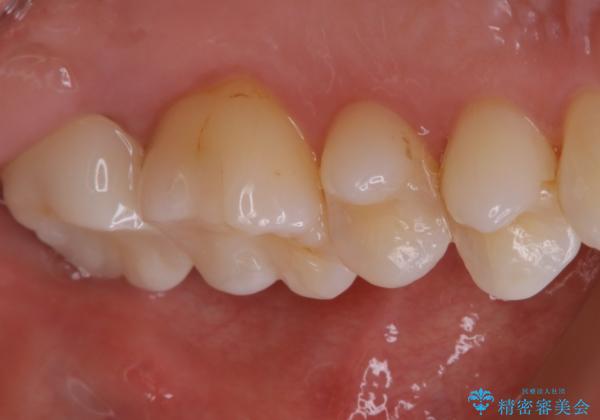

- 一番奥の歯に違和感がありご来院頂いた患者様です。

診断の結果、一番奥の歯は失活していたため精密根管治療から治療介入となりました。奥から2番目の歯にも大きな虫歯が認められたため、セラミックインレーによる補綴治療を行いました。 精密根管治療は患者様のご希望により、福本院長に行っていただきました。